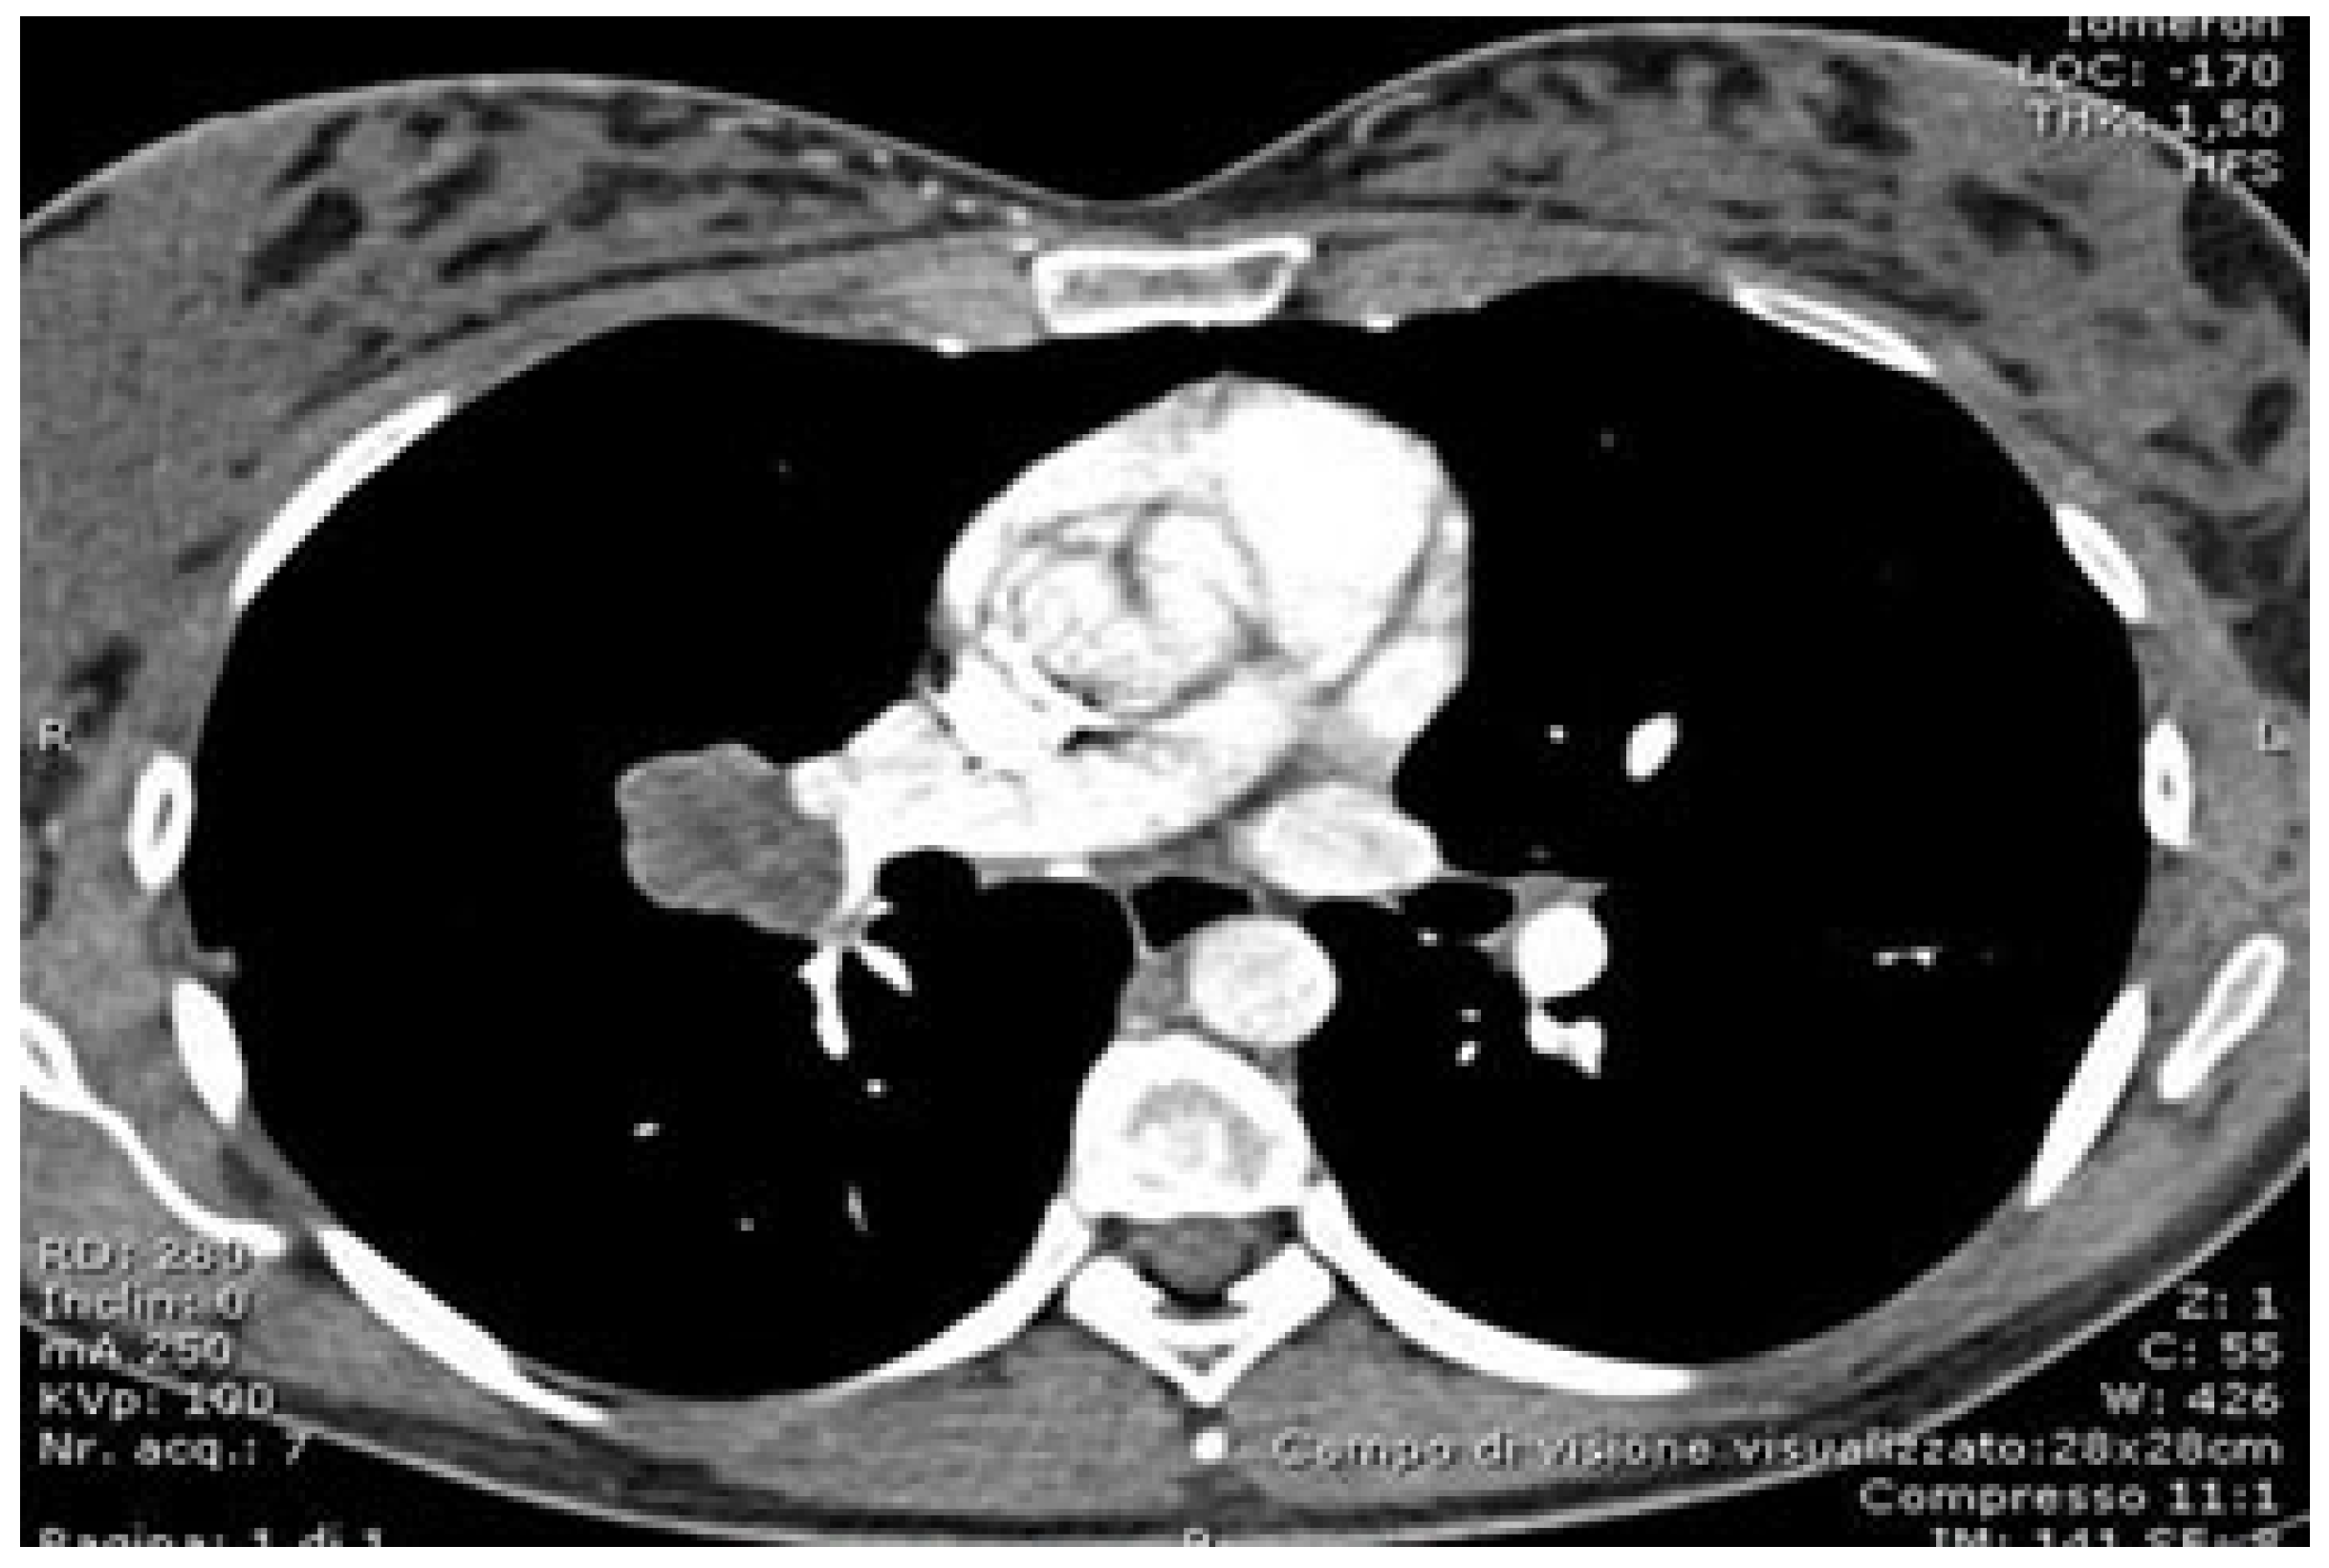

5.1. Preoperative Evaluation and Software in Robotic Surgery

5.2. Role of Advanced Software in Preoperative Planning

- Ikeda, N.; Yoshimura, A.; Hagiwara, M.; Akata, S.; Saji, H. Three dimensional computed tomography lung modeling is useful in simulation and navigation of lung cancer surgery. Ann. Thorac. Cardiovasc. Surg. 2013, 19, 1–5. [Google Scholar] [CrossRef] [PubMed]

- Chen-Yoshikawa, T.F.; Date, H. Update on three-dimensional image reconstruction for preoperative simulation in thoracic surgery. J. Thorac. Dis. 2016, 8 (Suppl. S3), S295–S301. [Google Scholar] [CrossRef]